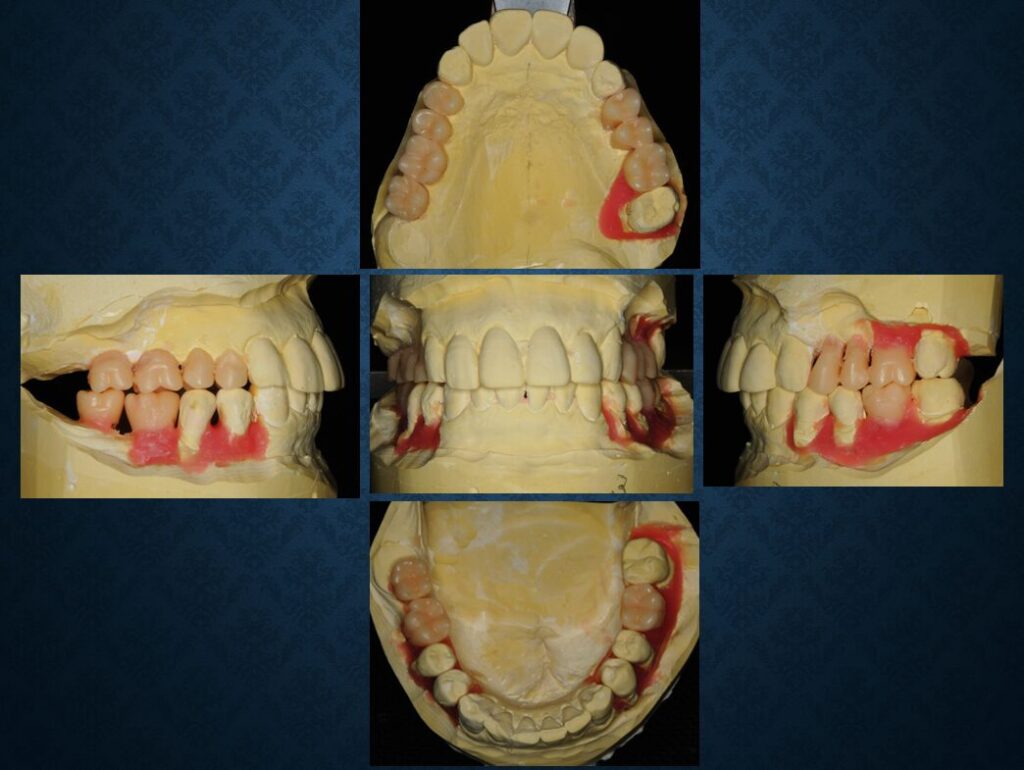

40代フィリピン人男性の方でした。欠損部には入れ歯が入っていました。インプラントに代えて欲しいというご希望でした。職業は会社経営、モデル、英会話教師、ボディービルダー、六本木警察フィリピン語講師、映画俳優など多岐にわたり、日本だけでなく、オーストラリア、台湾、スペインなどを渡り歩いている方でした。多忙を極めていらしたので治療は度々中断しましたが、無事にゴールできました。